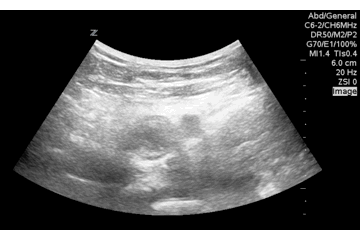

QA of the Day, Sono Stuff QA of the Day. Yes, she has a femoral DVT! Now turn down the gain! My eyes! #pocus #foamus Date: August 31, 2016Author: Mike 0 Comments Share this: Share on X (Opens in new window) X Share on Facebook (Opens in new window) Facebook Like Loading...